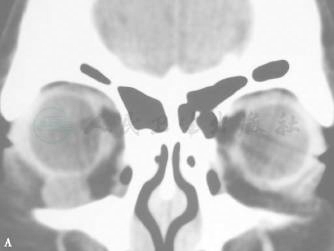

1.CT显示肿物呈囊性密度,边界清楚,多数无骨质改变,少数出现骨壁压迫改变(图4)。

图4 获得性结膜囊肿

A、B.冠状CT可见右眼球下方囊性密度影,边界清楚。